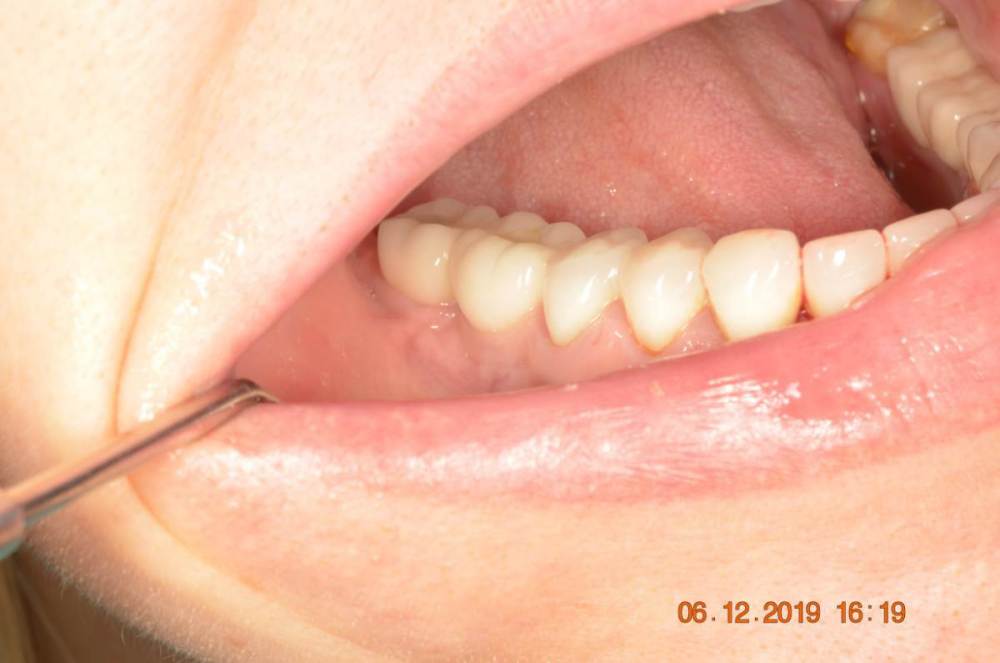

Большой Зеленый Опубликовано 15 августа, 2023 Поделиться Опубликовано 15 августа, 2023 Винтовая фиксация . 8 лет наблюдений .Полет нормальный. Немного прокрасились пломбы в шахтах. Пациентка довольна и счастлива. Привела уже вагон беззубых друзей и родственников. P/S. Система имплантов Ирис...:) 1 Ссылка на комментарий